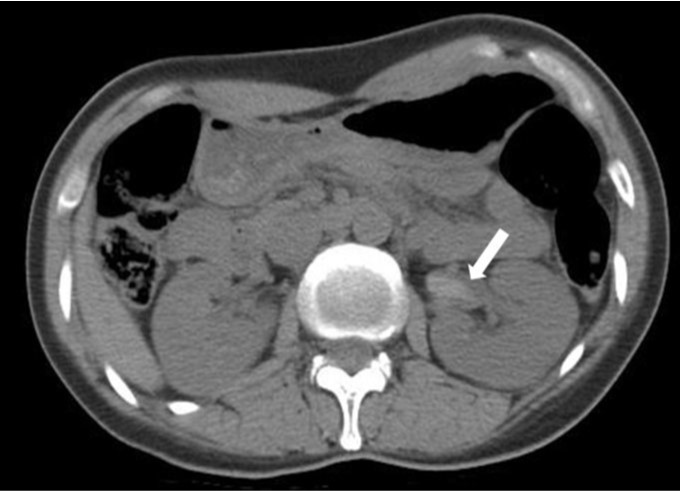

Fig. 1.

Axial pre-contrast CT image shows high density lesion (arrow) in the left renal pelvis and proximal ureter.